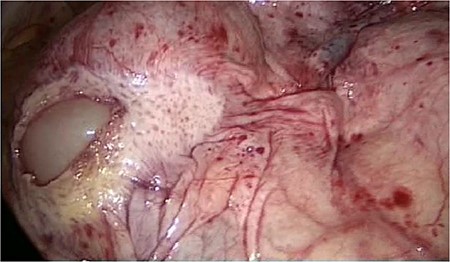

The slim intraperitoneal appendix in the left upper corner with the covered terminal ileum. In the right lower corner, the covered ileum convulse is seen.

Even the terminal ileum seemed to be retroperitoneal. The slim preperitoneal appendix and the terminal retroperitoneal ileum are demonstrated in Fig. 4. The entire ileum was covered by the peritoneum.